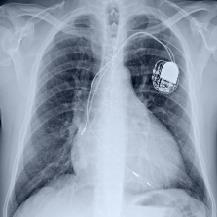

Thoracic disease detection from chest radiographs using deep learning methods has been an active area of research in the last decade. Most previous methods attempt to focus on the diseased organs of the image by identifying spatial regions responsible for significant contributions to the model's prediction. In contrast, expert radiologists first locate the prominent anatomical structures before determining if those regions are anomalous. Therefore, integrating anatomical knowledge within deep learning models could bring substantial improvement in automatic disease classification. This work proposes an anatomy-aware attention-based architecture named Anatomy X-Net, that prioritizes the spatial features guided by the pre-identified anatomy regions. We leverage a semi-supervised learning method using the JSRT dataset containing organ-level annotation to obtain the anatomical segmentation masks (for lungs and heart) for the NIH and CheXpert datasets. The proposed Anatomy X-Net uses the pre-trained DenseNet-121 as the backbone network with two corresponding structured modules, the Anatomy Aware Attention (AAA) and Probabilistic Weighted Average Pooling (PWAP), in a cohesive framework for anatomical attention learning. Our proposed method sets new state-of-the-art performance on the official NIH test set with an AUC score of 0.8439, proving the efficacy of utilizing the anatomy segmentation knowledge to improve the thoracic disease classification. Furthermore, the Anatomy X-Net yields an averaged AUC of 0.9020 on the Stanford CheXpert dataset, improving on existing methods that demonstrate the generalizability of the proposed framework.